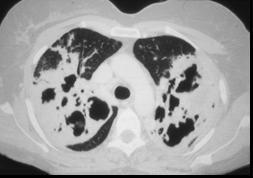

问题 一养鸽女,48岁,发热,咳嗽,咳脓痰带血半月余,请结合CT检查选出最可能的诊断 ( )

选项 A、间质性肺炎 B、支气管扩张 C、肺曲菌病 D、肺癌 E、原发性肺结核

答案 C